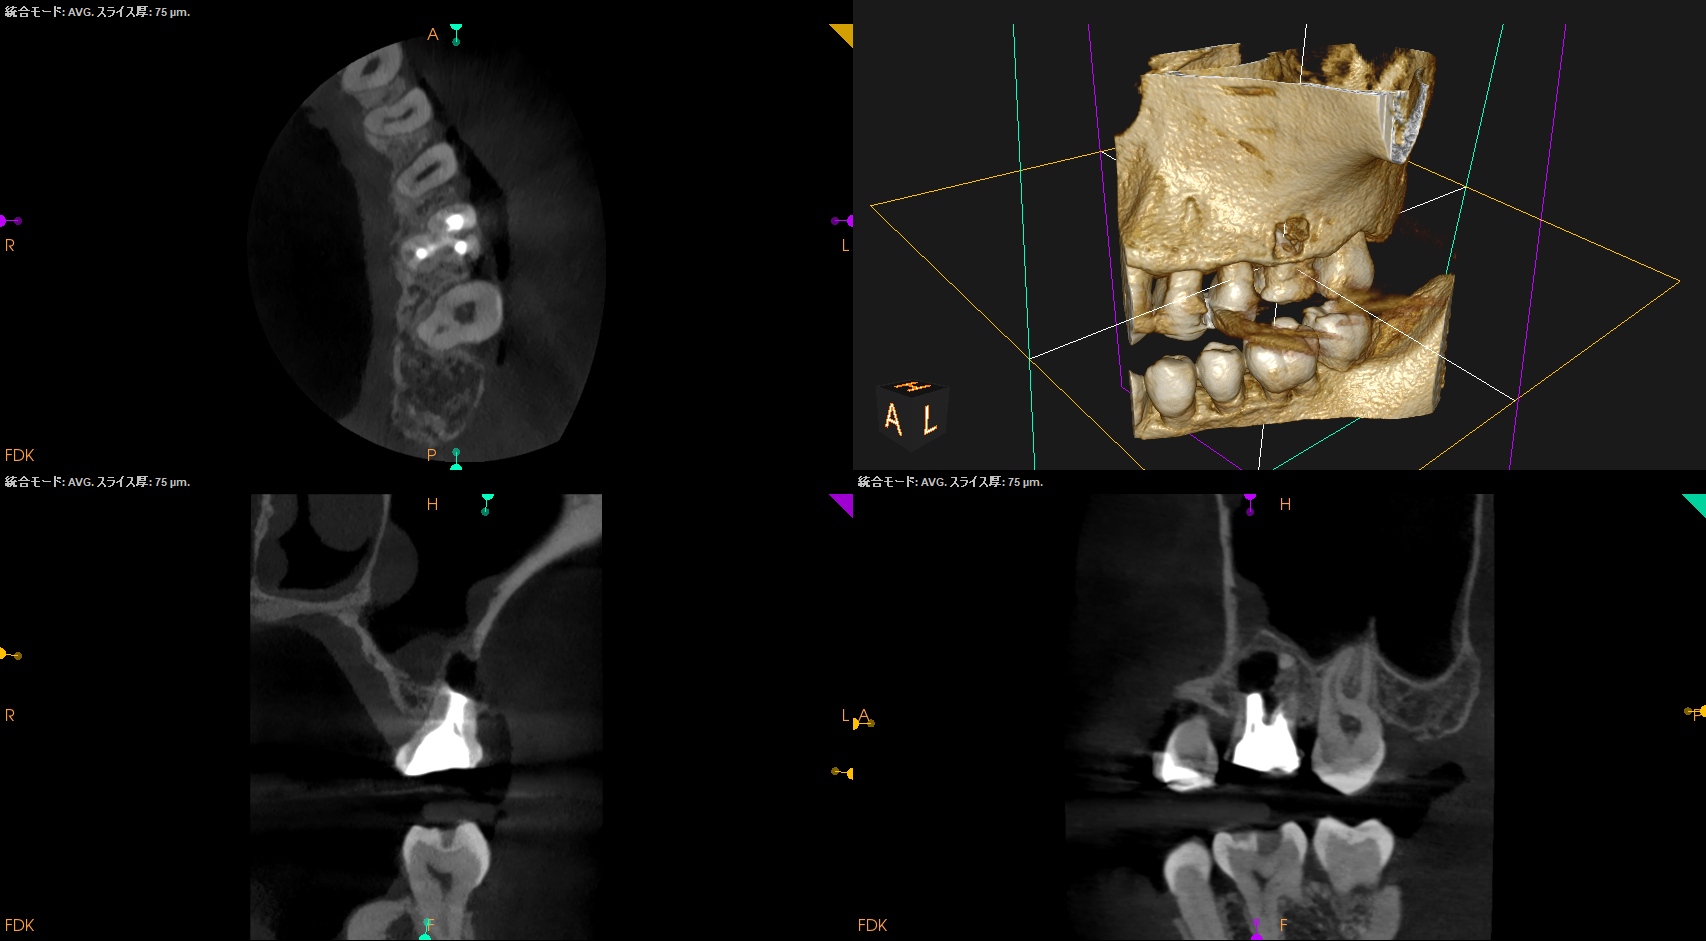

CBCT(2025.4.15)

MB

MBの根管口部あたりに穿孔が疑われる所見がある。

ストリッピングパーフォレーションというやつだ。

根充後に根管をBC Puttyで埋める必要があるだろう。

DB

P

DB,Pには何もない。

SelectiveにMBのみを扱う治療になるだろう。

さて、外科の際は

上顎洞の穿孔を避けるため、MBはCEJよりも5.6mm下方に1.3mm Osteotomyして頬舌的に4.3〜4.9mm切断する必要がある。

これはそれほど困難ではない。

その後、Root tipごと取り出す形になるだろう。